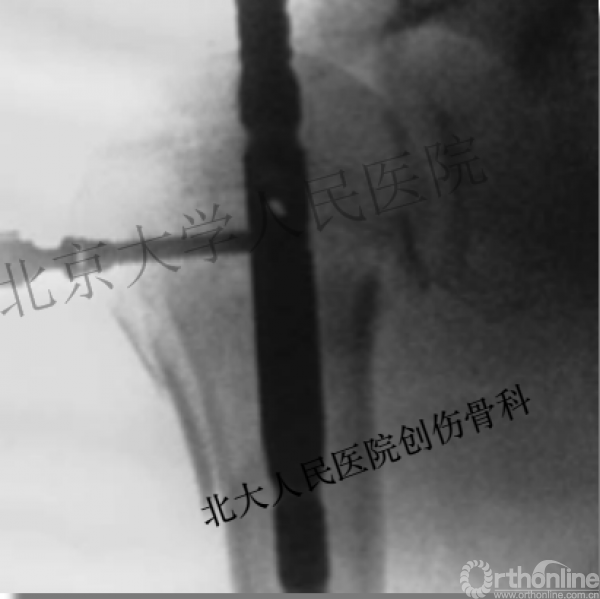

术中片